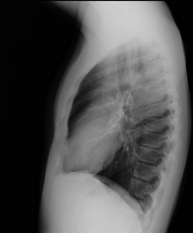

- Chest X-ray

A chest X-ray uses a small dose of radiation to obtain a two-dimensional image of the thoracic cavity and its contents (lungs, heart, mediastinum, etc.). It is one of the most commonly performed medical tests.